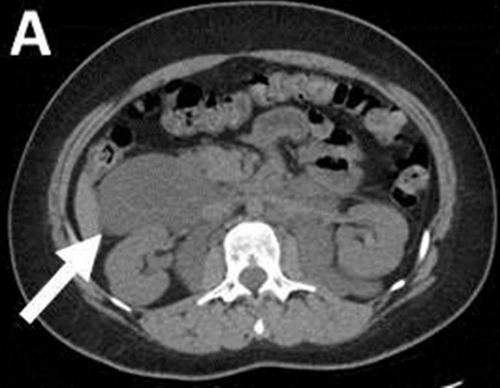

Angiomiolipoma renal à direita

Angiomiolipoma renal bilateral

Angiomiolipomas renais